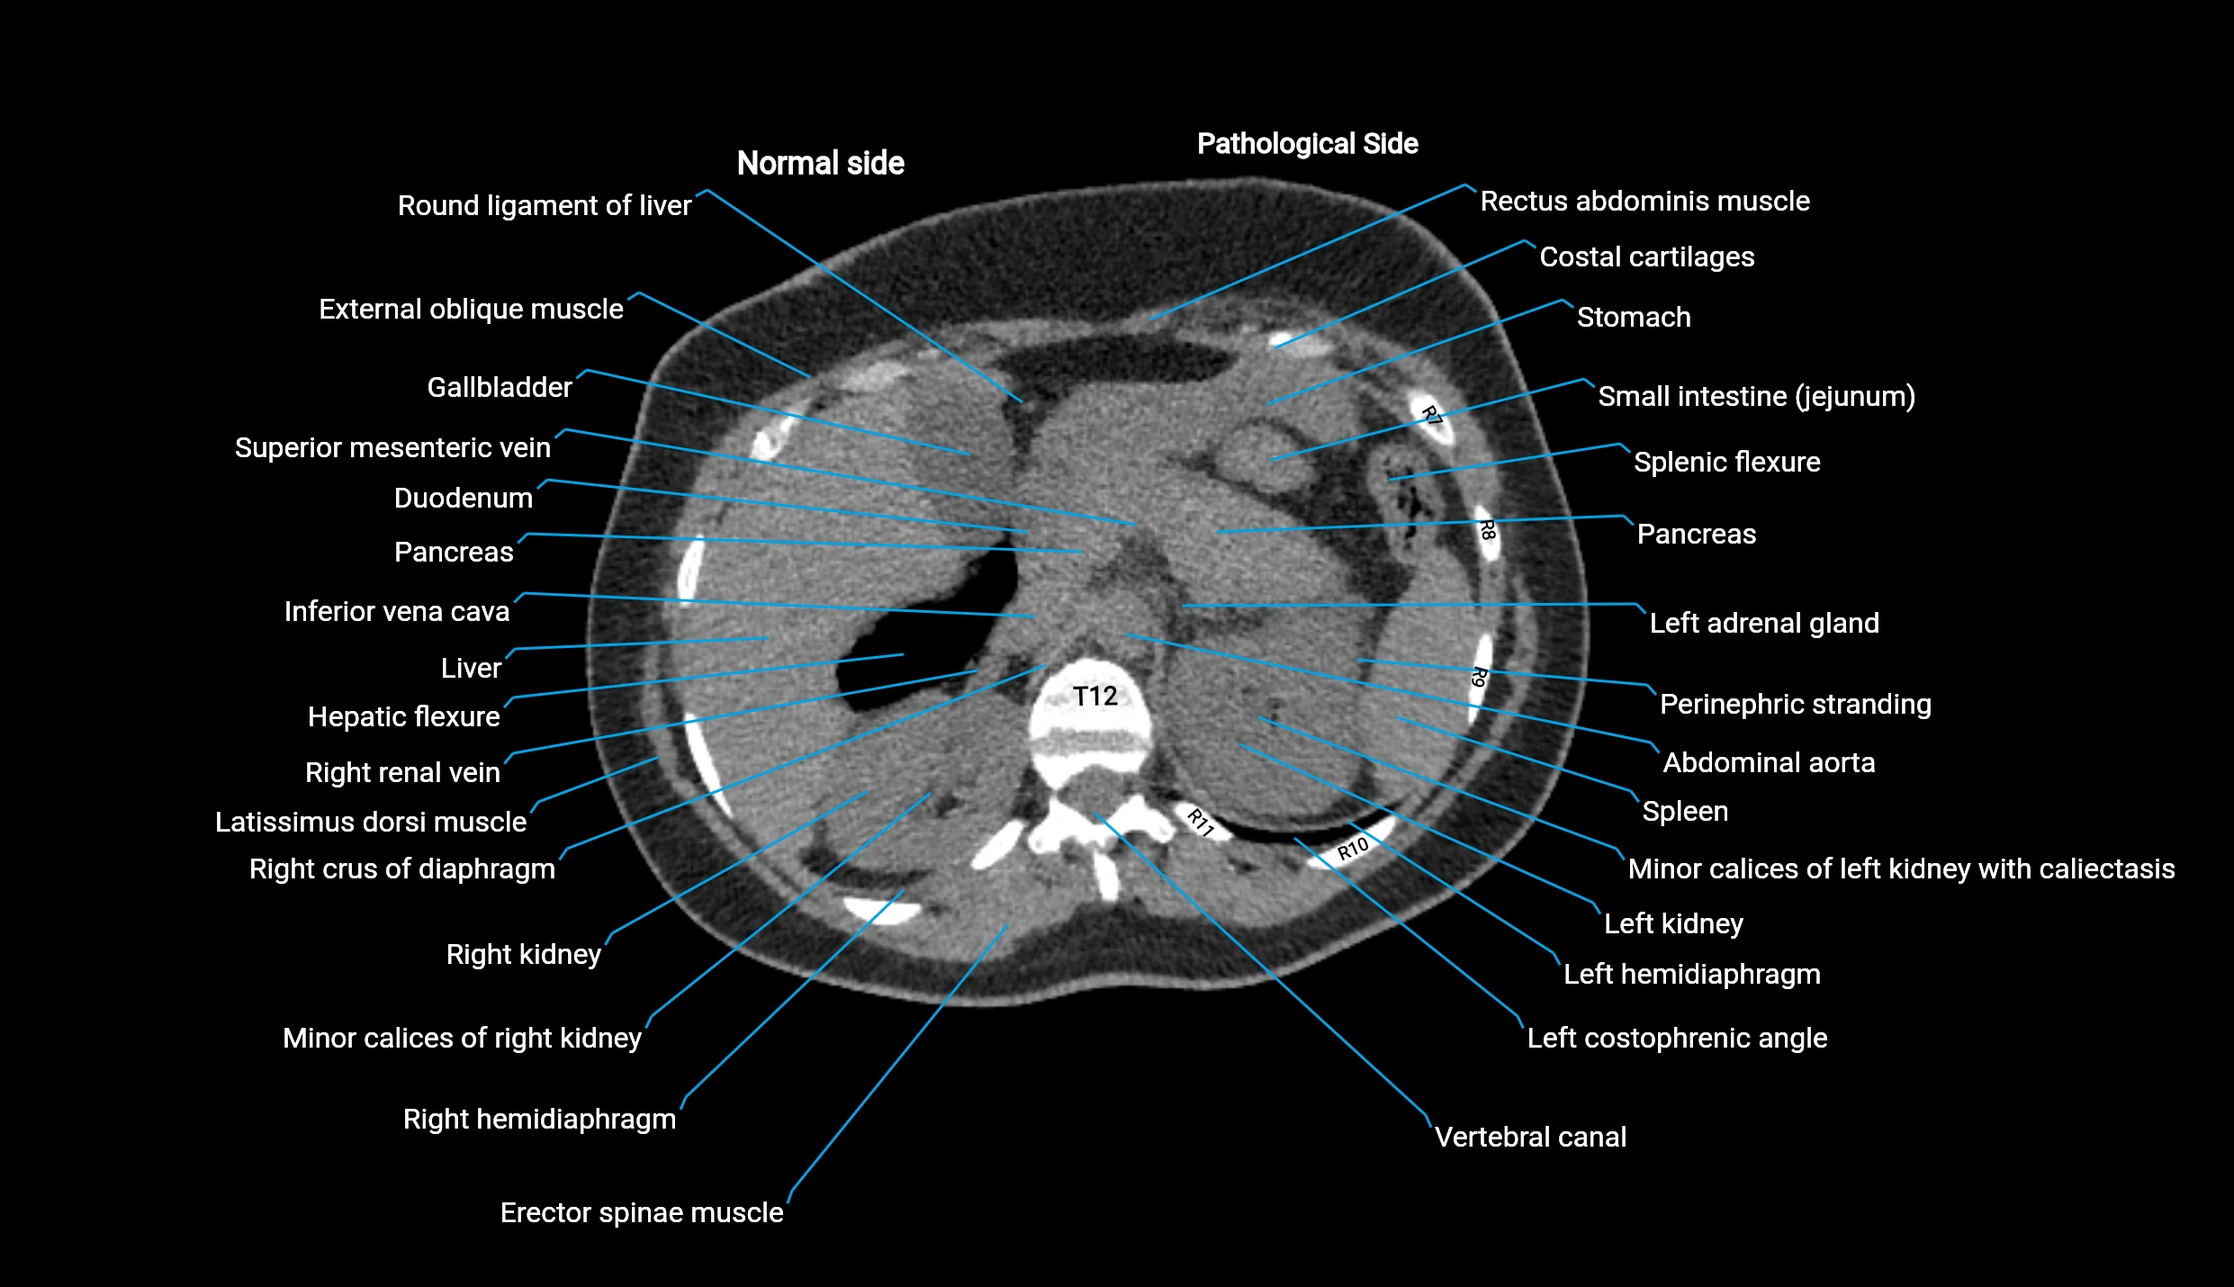

Post-Contrast CT (Contrast-Enhanced CT):

• Portal venous phase:

• Anterior right portal branch enhances intensely and homogeneously

• Clearly separates from posterior branch

• Branching pattern to segments V and VIII sharply defined

• Arterial phase:

• Slight enhancement but less conspicuous than in portal phase

• Coronal and sagittal reconstructions:

• Optimal visualization of segmental bifurcation

• Used for preoperative liver mapping

• CT liver segmentation:

• RAPV acts as the principal boundary landmark for dividing anterior vs. posterior right hepatic segments